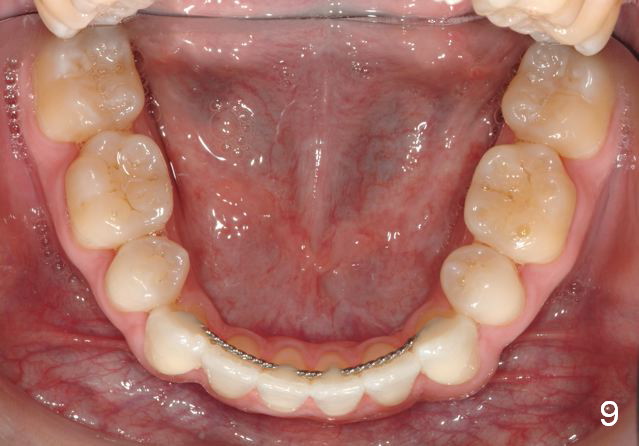

Final photos are taken on 03/23/2016. Mid face deficiency improved, now just a hint (Fig.3). Before (Fig.4,10) and after (Fig.5-9) occlusal adjustment of the canines.